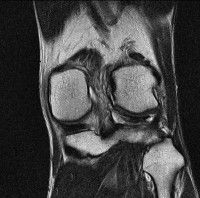

무릎 mri 간단히 봐주실 수 있으시나요 ㅠㅠ

안녕하세요 8년전 십자인대 수술하고 최근 무리한 운동에 무릎 불편감이 생겨서

mri 찍었습니다.

진단결과는 첫 찍은 병원에서 활액막염 이라는 진단을 받았습니다. 혹시 봐주실 수 있으실까요?

진단결과가 달라 혼란스럽습니다 ㅠㅠ

• 안녕하세요. 강성주 의사입니다.

올라온 MRI가 단편적이라서 정확한 진단에 어려움이 있지만 십자인대에는 큰 이상이 있지는 않은것 같으며, 무릎관절내 물이 있는 것으로 보아 활액막염의 진단이 맞을 것 같습니다.

하지만 단편적인 영상이기 때문에 촬영병원에서 정확한 판독지 등을 받으시는 것이 좋겠습니다.